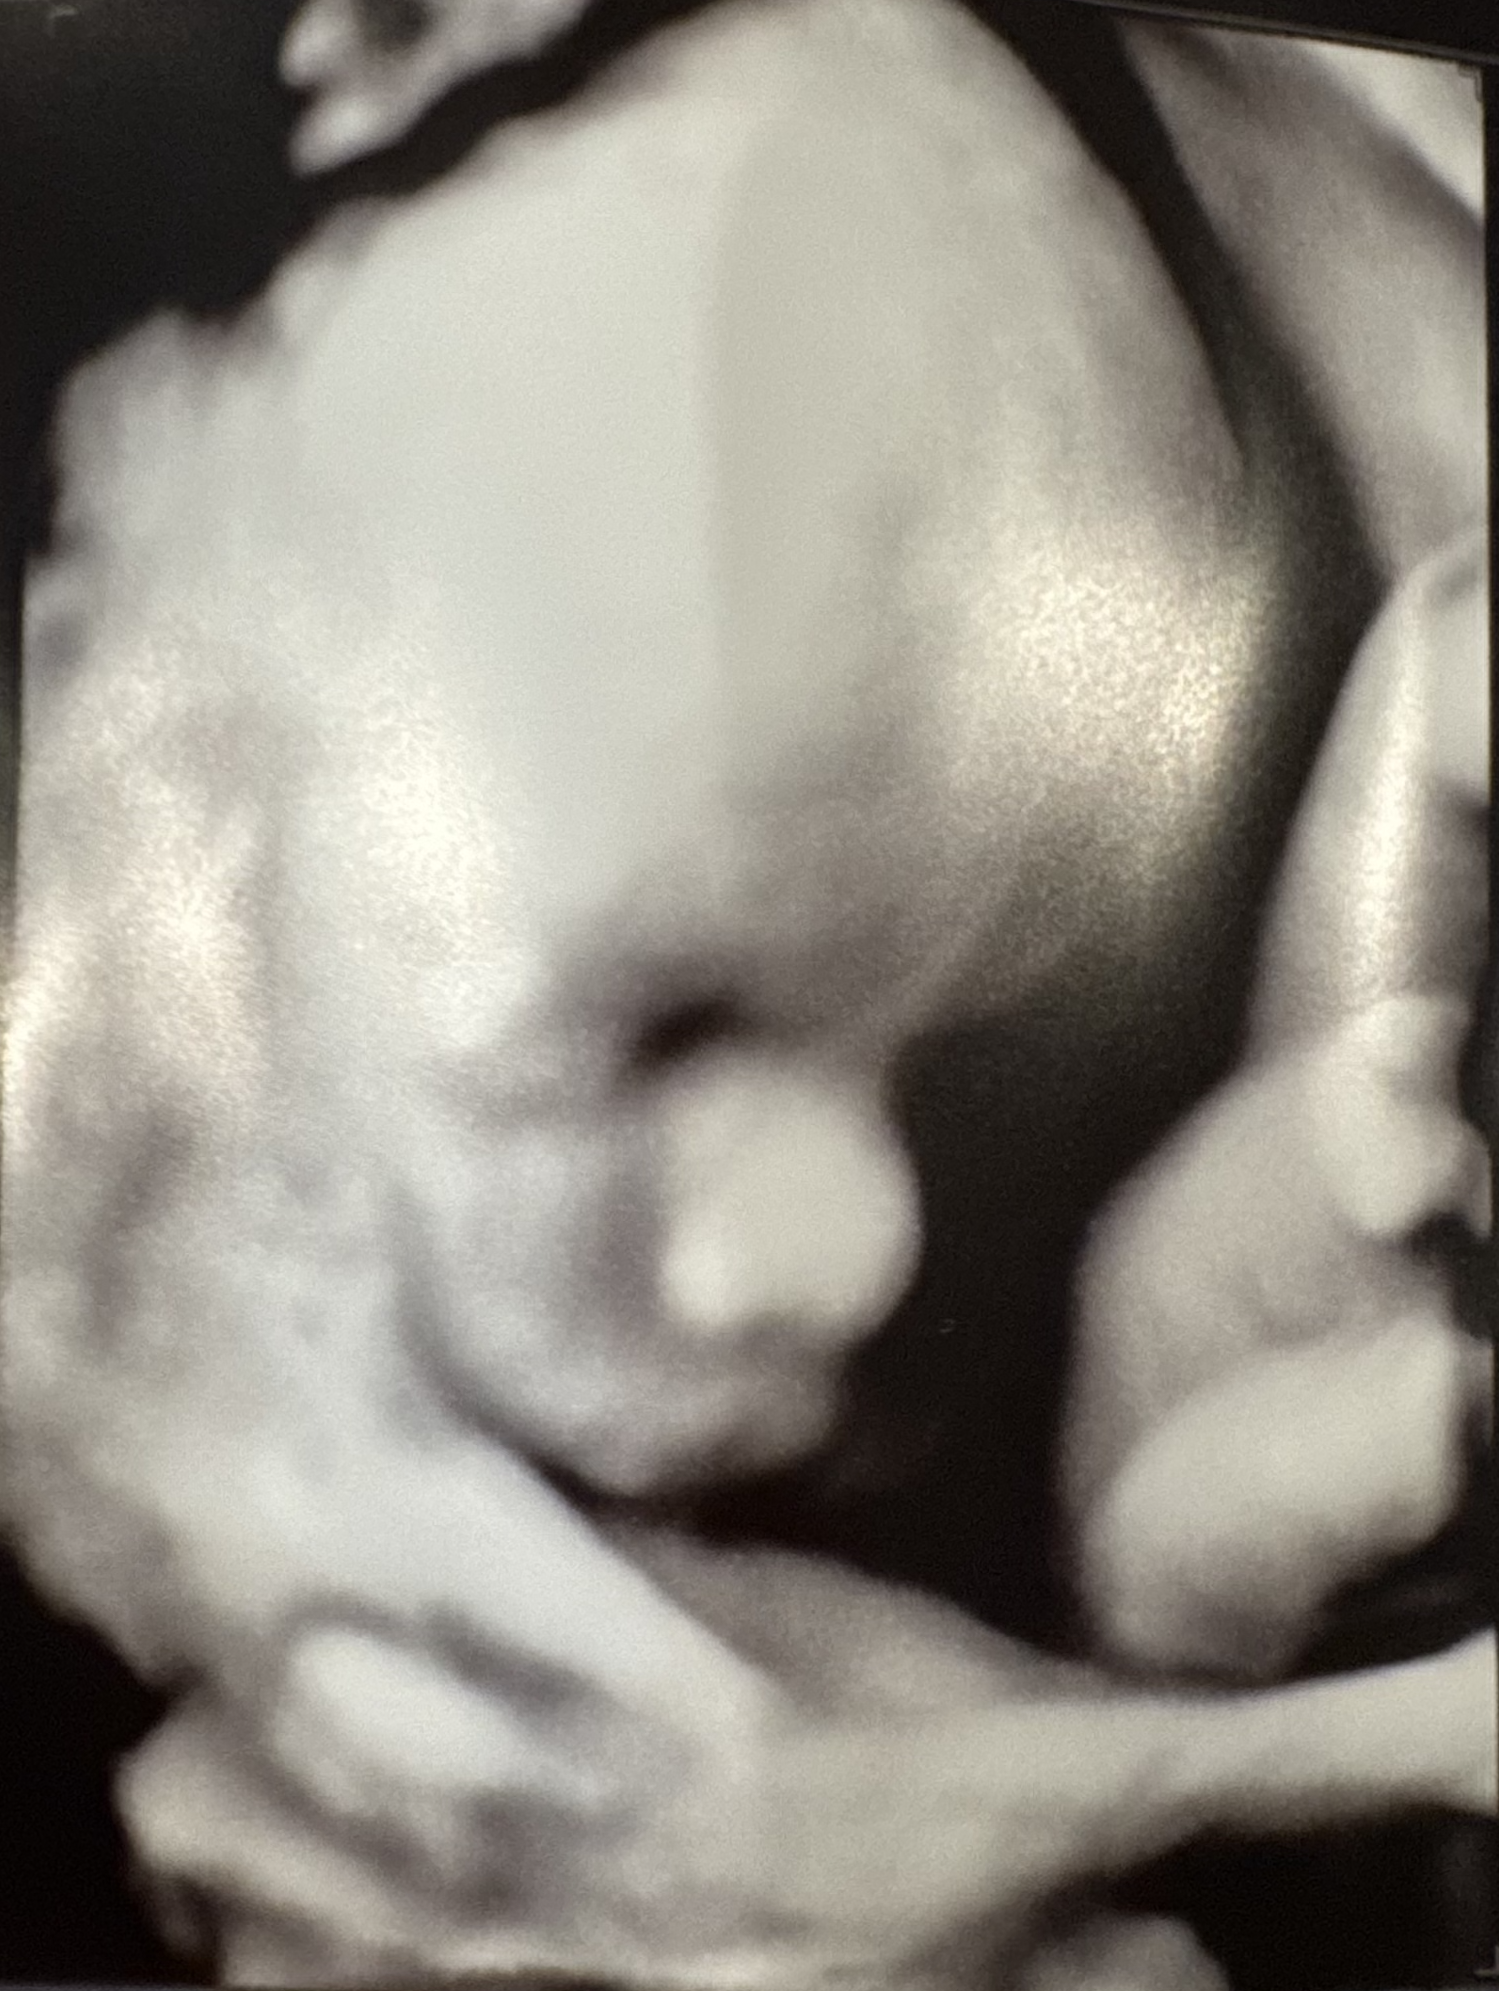

This might be a short On the Record; I woke up a bit late and today is Audra's baby shower. That doesn't mean I'm going to go easy on you, or on myself.

It's an odd feeling to be roughly two months away from your first child being born. Audra and I began trying to have kids in another life, way back in 2018. I was incredibly ill and it may not have been the most responsible thing to do, but then this isn't a reasonable desire, is it? My illness made it quite difficult for a number of biological reasons. I underwent surgery – twice – in an attempt to get a step closer, to no avail.

After my transplant, gluttons for punishment that we are, we began to try again. Audra got pregnant in July 2020 via IUI. For a few months, we were stunned by our fortune. I had received a transplant before Covid hit, we were building a house, and despite everything being shut down, we got pregnant with the help of science.

We lost the baby in the second trimester. The baby was not genetically viable. This, we learned, is one of the downsides of IUI: there's no genetic testing component. You're at the mercy of Mother Nature, and she's ruthless, unapologetic, and final. I recorded a short episode of Sonder Union about this time.

It took nearly a year to pick ourselves up and think about trying again. This time armed with the hard-won understanding that genetic testing is a critical component to ensuring we don't repeat a mistake, we moved on to IVF, where science plays a confidence game with Mother Nature – pretending to be in control, while holding on for dear life.

Audra and I went through another three rounds of IVF. This is more trying than you can imagine, if you haven't done it yourself. Emotionally, it guts you, dries you out, and leaves you desiccated. We went on for three straight years pretending that things were normal, only to find that the insanity of the whole thing in fact became normal. On our journey, we exhausted the ways IVF could go wrong until, to our disbelief, an embryo implantation had taken.

Going into the transfer procedure, we'd agreed that if this one didn't take, we were done. We had come to terms with not having a child: we were happy as-is. So, as we sat in the clinic on Halloween waiting for the doctor to come in and transfer the embryo, Audra asked me to play some music to take her mind off her ludicrously full bladder. Rather perversely, I opened Tidal and played Taylor Swift's "All Too Well" for reasons I cannot explain. We sat in that lavender room, laughing about the absurdity of the moment, content with the inevitable failure of the procedure and ready to move on.

And here we are, seven months later, boxes of strollers and pack-and-plays littering the house, getting ready to see friends, family, and loved ones come together to celebrate simultaneously the least likely and most fought-for baby in the family. I cannot say that we are without our hesitations; we had, after all, come to terms with a childless life, and now this child is bursting onto the scene.

It is also true – two contradictory things can be true at once! – that we are incredibly excited to be having a little boy in a few months.

So here we are, little man, willing a world filled with love into existence for you. Look at all these people coming out just to say hello!